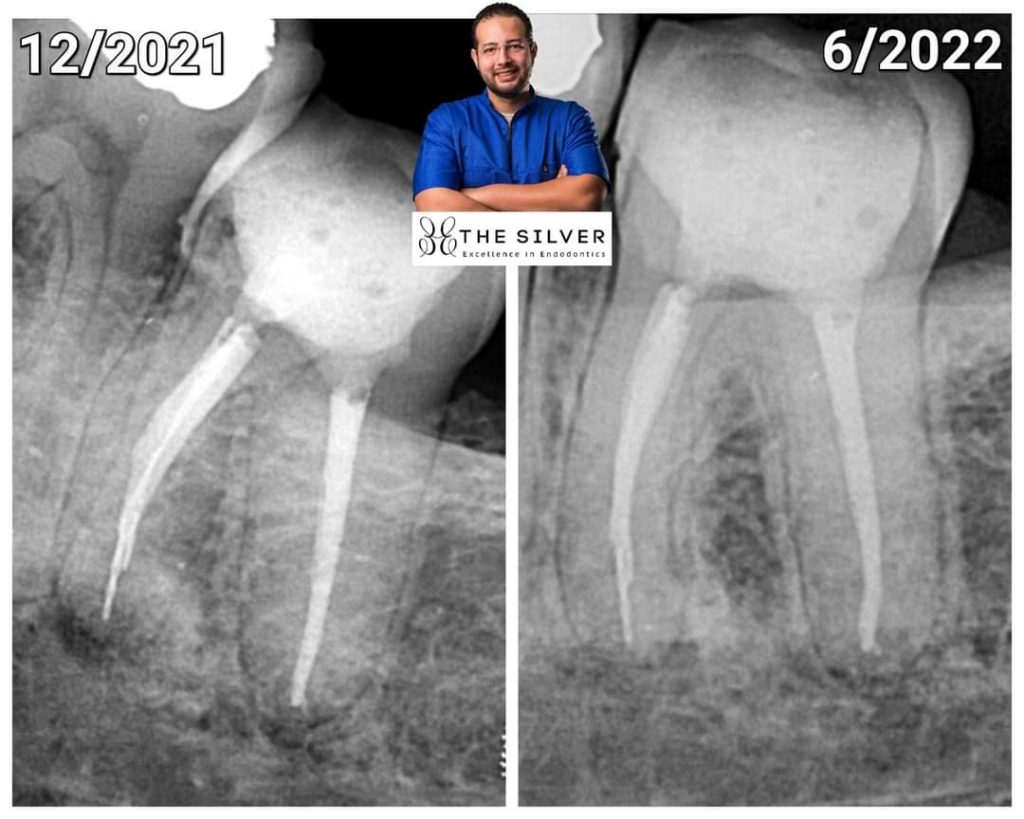

I was doing a Retratment for lower 2nd molar with acute apical periodontitis with large metal post in the distal canal…

I removed the post start removing Gp… all was fine… until last shaping File while recapitulate with 15 k file it breaks 🙃

Trying to bypass with 10k file…. it also breaks 😵💫😵💫

What we agreed to do is to obturate and apply resin modified GIC as a semi-permanent restoration until his next vacation in the summer…. and if feels any symptoms … he will contact a colleague in his country to manage the case…

Surprisingly…. after 7 months…. the patient came… tooth fully functional…no symptoms

And the Lesion Healed..😮🤪

2- the tooth is obviously has acute apical periodontitis

4- the broken instrument is at the apex…

In fact it fructured when the file reached full working length which means it’s exactly at the apex

5- i used bioceramic sealer ( Endoseal MTA by Maruchi A true MTA in sealer)